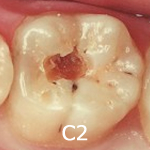

C2(象牙質に達するむし歯)- エナメル質より内側にある象牙質に達した虫歯です。まだ神経には達していない状態ですので、激しい痛みはありませんが冷たいものや甘いものがしみ始めます。金属または白い材質によって削って詰める治療を行います。